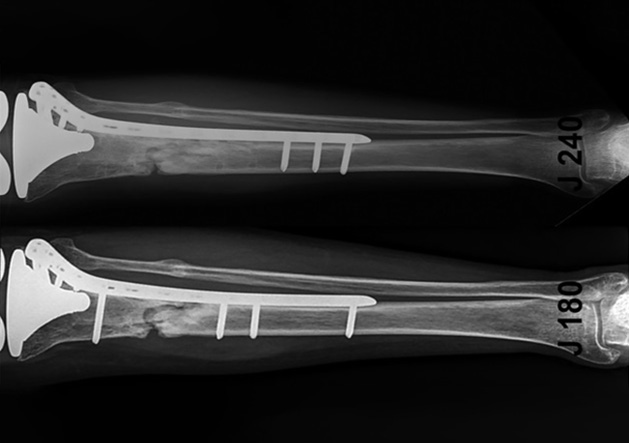

기존 골고정장치와 유연하게 연동될 수 있는

초소형 AI 기반 의료기기를 개발하고 있습니다.